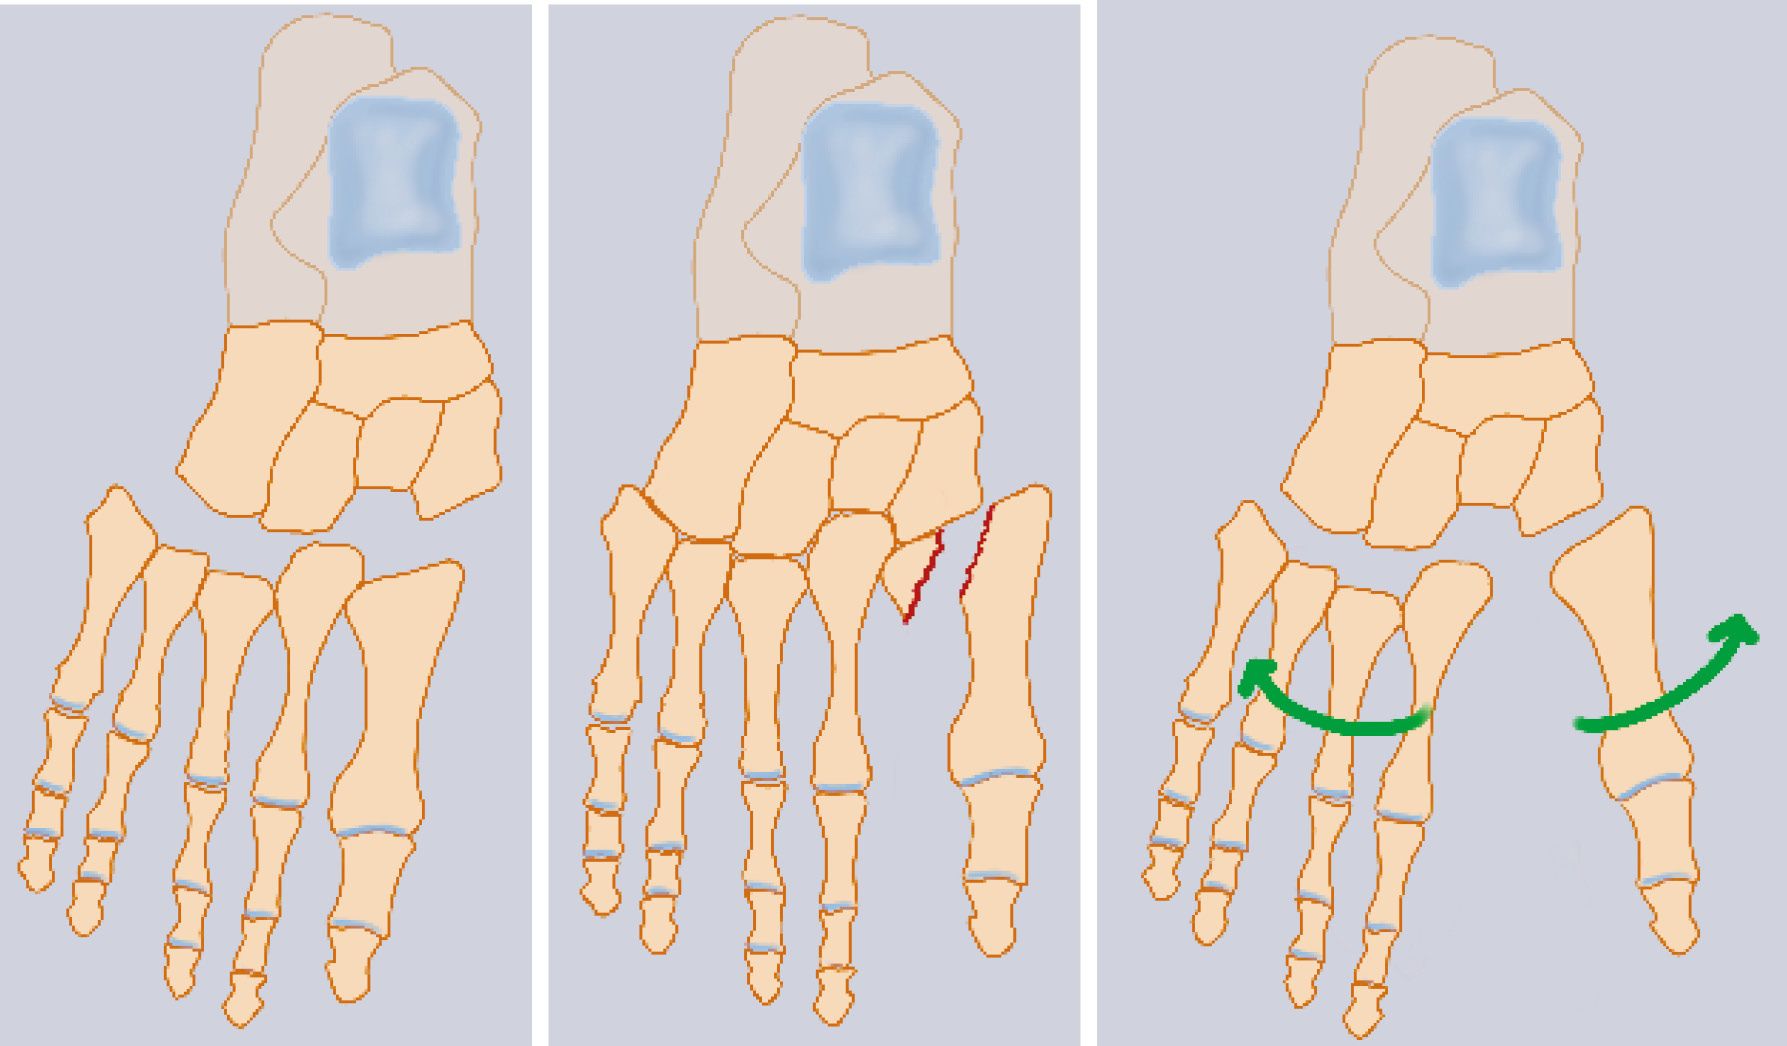

An appreciation of the functional anatomy of the complex set of bony and ligamentous structures forming this joint is imperative for the proper assessment and treatment of Lisfranc fracture-dislocations. This joint is characterized by a quasi-immobility of the middle compartment, in particular of the second metatarsal bone whose base is impacted between the cuneiform bones. This explaines, in case of dislocation force, the relative frequency of M2 base fractures (Fig 4).

The weaker dorsal ligament structures rupture first. Fracture-dislocation occurs if the metatarsals fracture and/or the plantar ligaments rupture. More than two thirds of these injuries are caused by road traffic accidents, followed by high falls (20, 21). Furthermore, it has been shown that a dorsal flexion moment applied during axial compression of the foot leads to subsequent dorsal and then lateral dislocation of the TMT joint. (17)

Low-energy injury mechanisms, usually during sporting activity, result from indirect trauma and are more subtle in their clinical presentation. (18, 19) Sports such as football or horse riding are the source of these injuries. (16,22) Dorsal dislocations usually result from hyperflexion of the forefoot, plantar dislocations from a shearing movement, after a fall on the hind foot.(Fig 6)